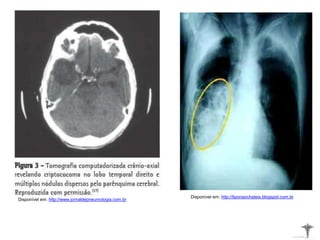

• Estão relacionadas ao Sistema Nervoso Central;

• Infecção pulmonar ou manifestações discretas semelhantes ao

quadro gripal;